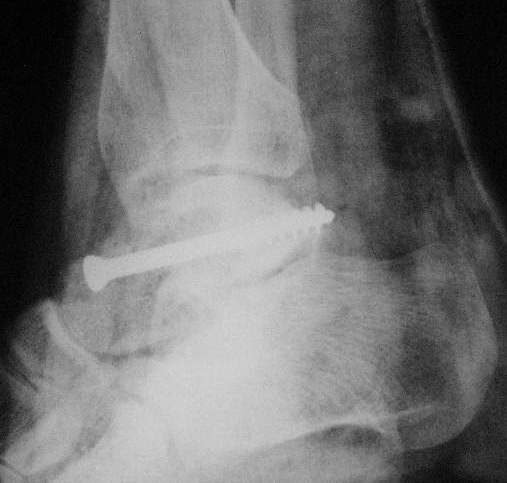

Здесь на фото примеры:

Переломовывих тарана с повреждением медиальной стороны. Через 4 часа после поступления проведена репозиция и фиксация тарана после Irrigation&Debridment. Частичное несращение медиальной лодыжки не беспокоит, вернулся к активному образу жизни. Полная нагрузка разрешена через 11 недель. Финальные снимки через 11 месяцев.